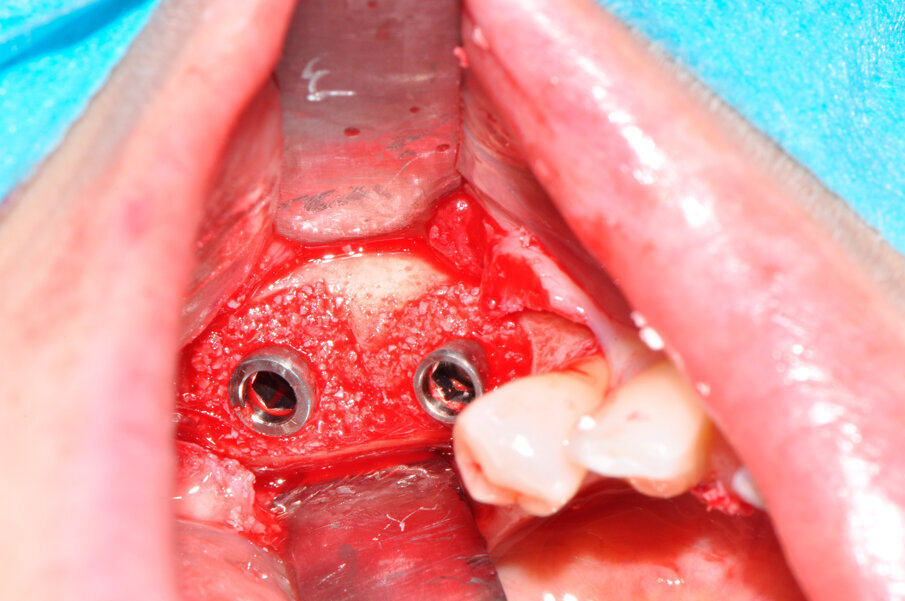

Il caso in esame riguarda una paziente di 53 anni, fumatrice, che si presentava all’osservazione per il consueto controllo periodico lamentando sanguinamento e dolore gengivale durante le manovre di igiene orale a livello di due impianti situati in posizione 4.6 e 4.7. A seguito dell’esecuzione di una CBCT per altri motivi si è potuto evidenziare un marcato riassorbimento osseo perimplantare (Fig. 1). Come si può osservare durante la chirurgia (Fig. 3) l’esposizione della superficie implantare è superiore al 50%. In entrambe le fixture con un maggior coinvolgimento in posizione 4.6. È stata inoltre riscontrata una sofferenza della mucosa attorno ai monconi delle due fixture.

Il ponte cementato e i monconi implantari sono stati rimossi per procedere all’apertura del lembo mucoperiosteo ed esporre totalmente gli impianti e la superficie ossea; l’esame clinico confermava l’entità del riassorbimento osseo già osservata all’esame radiografico (Fig. 3). Una volta rimosso il tessuto granulomatoso sviluppatosi intorno agli impianti (Fig. 4), si è eseguito un debridement perimplantare con conseguente rimozione meccanica delle spire esposte. La superficie dell’impianto è stata ripulita con air polishing, polvere di glicina e lucidatura finale (Fig. 5). Il letto osseo perimplantare è stato cruentato per stimolare l’angiogenesi e l’integrazione con l’innesto. Il granulato, precedentemente idratato, è stato innestato nel difetto osseo a coprire le spire della superficie esposta di entrambi gli impianti fino a ripristinare il profilo osseo originale (Fig. 6).

Fig. 3 - I due difetti perimplantari all’apertura del lembo.